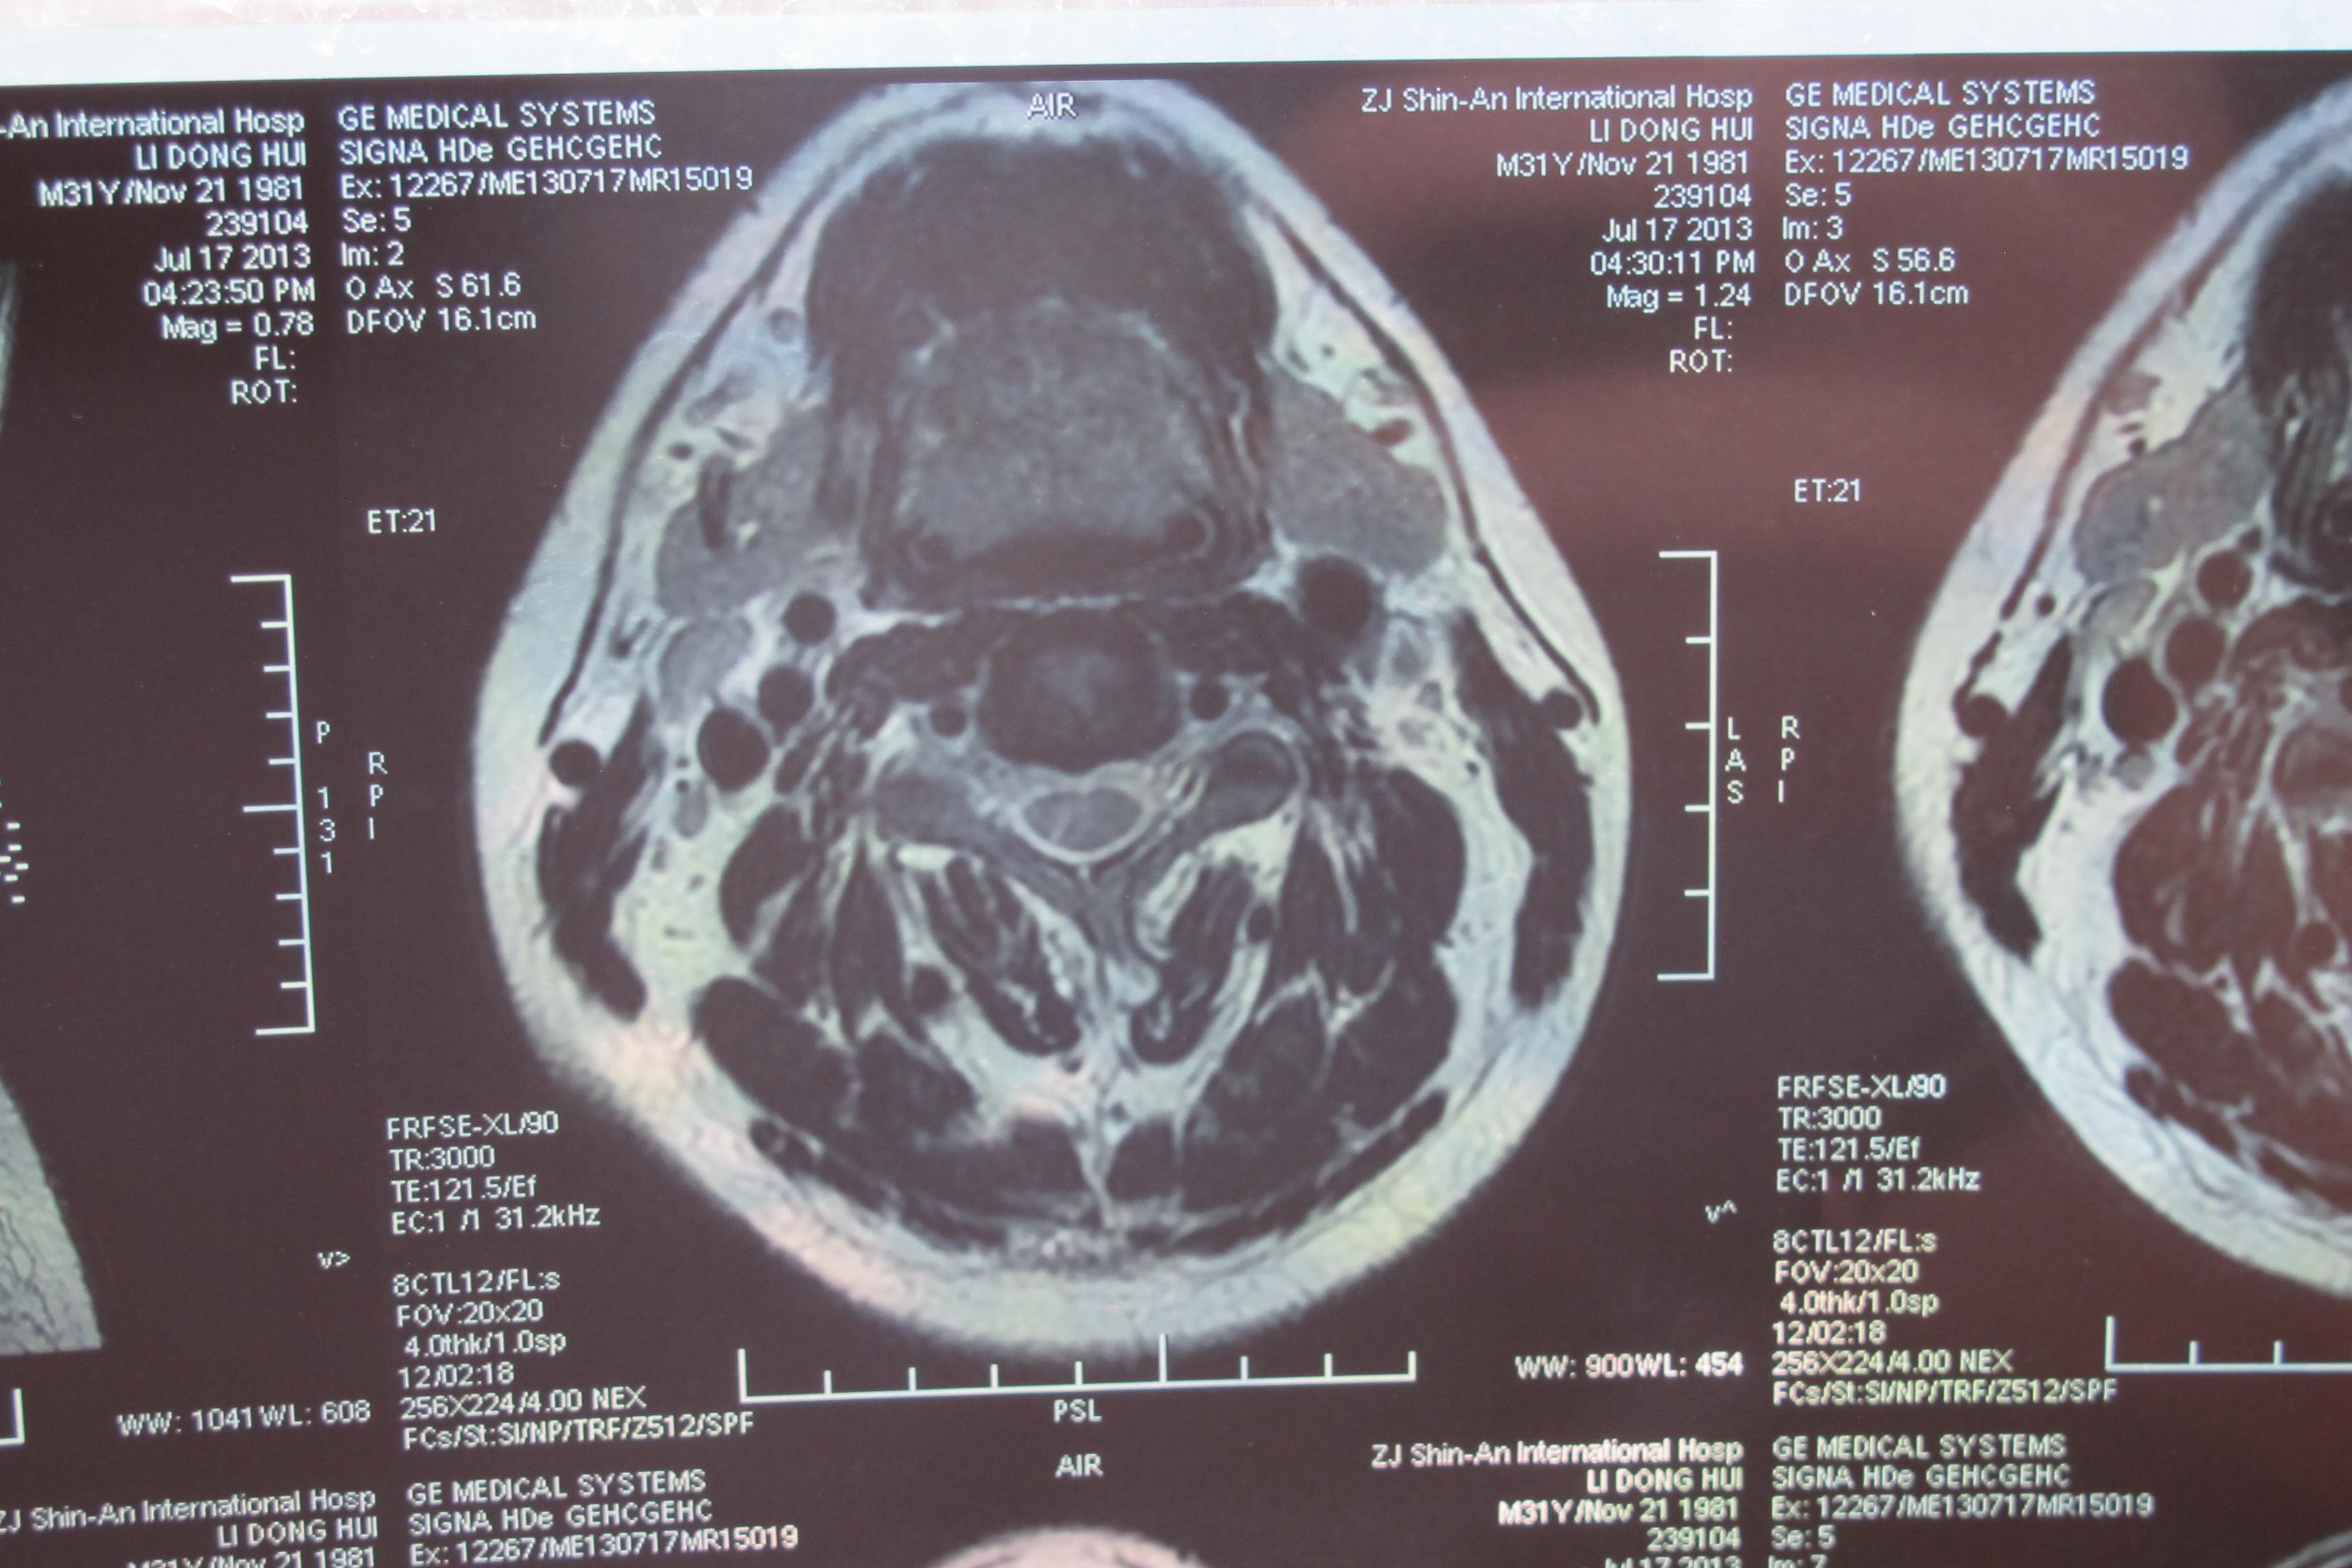

年轻多节段椎间盘突出颈椎病的治疗【1119】 [精华]

图片尺寸3648x2736

颈椎核磁片显示:颈4,5,6,7位颈椎间盘突出!